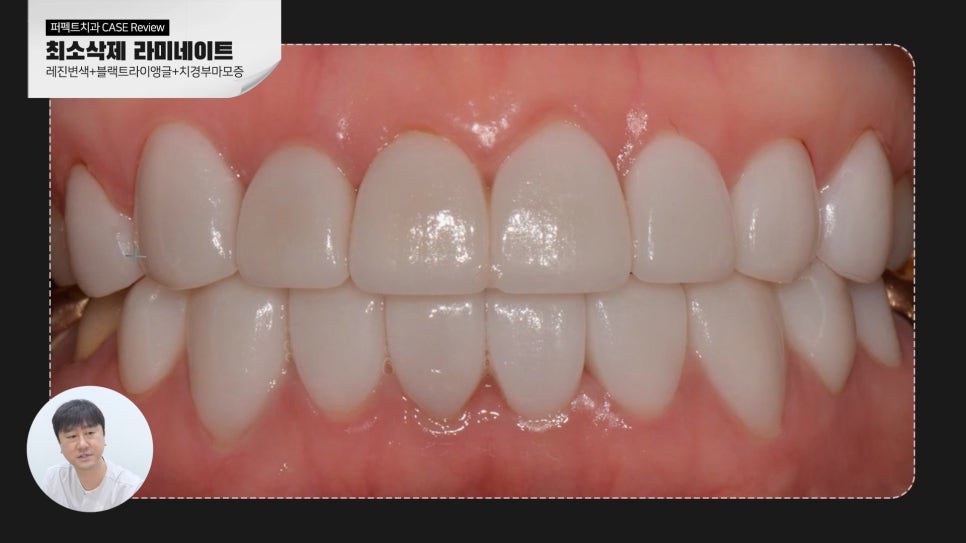

라미네이트를 통해 환자분이 개선되길 원하셨던 치아 사이 틈을 메꾸고 전보다 더

밝은 치아를 원하셨기 때문에 요구사항에 맞추어 치료를 진행했습니다.

가지런하고 고른 치열을 가지고 계셨기 때문에 0.1mm 최소삭제로 진행했는데요.

삭제량이 많이 않고 환자분께서 원하시던 목표에 도달하였기에 치료 결과에 크게 만족하셨습니다.